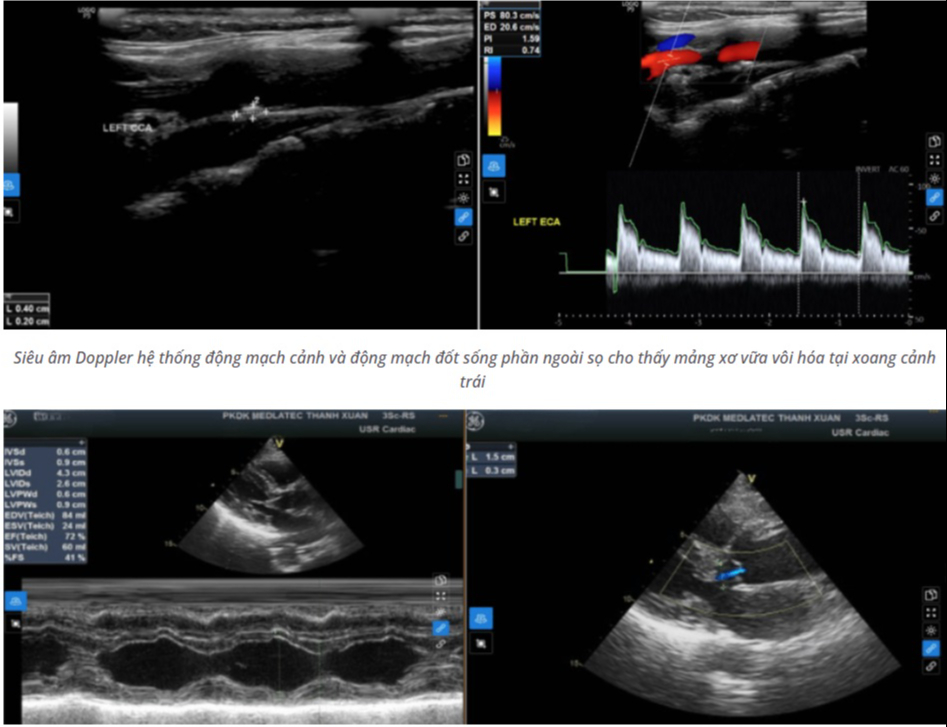

Siêu âm Doppler hệ thống động mạch cảnh và động mạch đốt sống phần ngoài sọ phát hiện mảng xơ vữa vôi hóa tại xoang cảnh trái, gây hẹp lòng mạch không đáng kể. Siêu âm tim ghi nhận hở nhẹ van động mạch chủ.

Siêu âm Doppler hệ thống động mạch cảnh và động mạch đốt sống phần ngoài sọ cho thấy mảng xơ vữa vôi hóa tại xoang cảnh trái